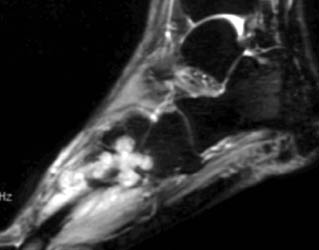

MR findings- Synovial proliferation with synovial fluid demonstrating as inhomogeneous high signal intensity on T2W images. Hemosiderine deposition is seen as low signal intensity foci on T1W and T2W images. Cystic bony erosions are present in fifty percent of patients.

26 years old female presenting with painful soft tissue mass at the plantar aspect of the left foot.MR demonstrates this mass is isointense on T1,isointense to minimally hyperintense on proton density and hyperintense on T2 W and Stir images. Bony erosions are identified in 3rd cuneiform, cuboid and bases of 3rd and 4th metatarsals on MRI and plain radiographs.Few foci of low signal intensity hemosiderine deposits are identified on all pulse sequences.